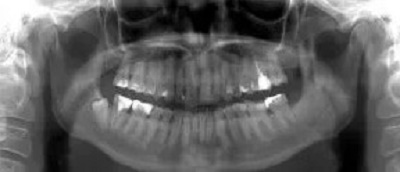

Pracownia RTG Profim specjalizuje się w rentgenodiagnostyce twarzoczaszki. Badania wykonywane są przede wszystkim na potrzeby diagnostyki stomatologicznej i laryngologicznej. Pacjenci poddają się im ze względu na konieczność leczenia chirurgicznego, zachowawczego, ortodontycznego i protetycznego. Aparatura używana w pracowni umożliwia m.in. wykonywanie badań RTG zewnątrzustnych i wewnątrzustnych. Diagnostyka zewnątrzustna to:

-zdjęcia pantomograficzne,

Przykładem zdjęć wewnątrzustnych wykonywanych w pracowni są zdjęcia punktowe zęba, skrzydłowo-zgryzowe i zgryzowe.